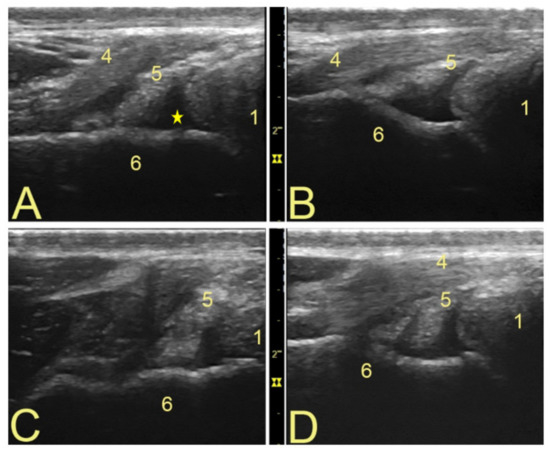

3.1. Anatomical Landmarks for Probe Positioning and Technical Settings

3.2. Popliteal Complex Characteristics